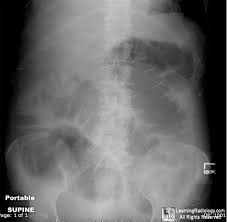

Rigler Sign

See the outline of the small and large bowel outlines - outlined by intraperitonial gas

Free air - Best seen in the right upper quadrant